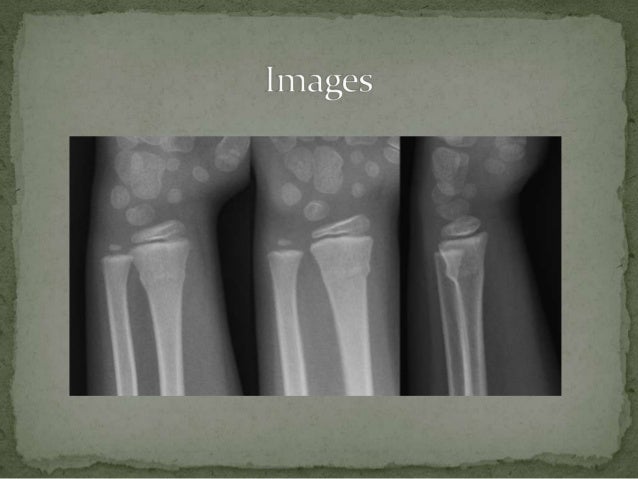

Torus Fracture | PPT

Torus Fracture | PPT www.slideshare.net